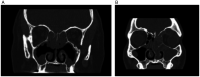

Results: A total of 356 patients had scans available for review; 80 (23%) patients were categorized into the AFRS group, 101 (28%) in the AERD group, 43 (12%) in the CCAD group, and 132 (37%) in the CRSwNP NOS group. Septal inflammatory involvement and oblique middle turbinate orientation on CT scans was higher in both AERD patients and CCAD patients as compared to AFRS and CRSwNP NOS patients (P < .05). Olfactory cleft opacification was increased in the AERD group compared to all other diagnoses (P < .05). The CCAD group showed lower LM scores compared to all other groups (P < .05), and the AFRS group revealed the greatest differences between left and right LM grades, representing unilaterality of disease (P < .05).